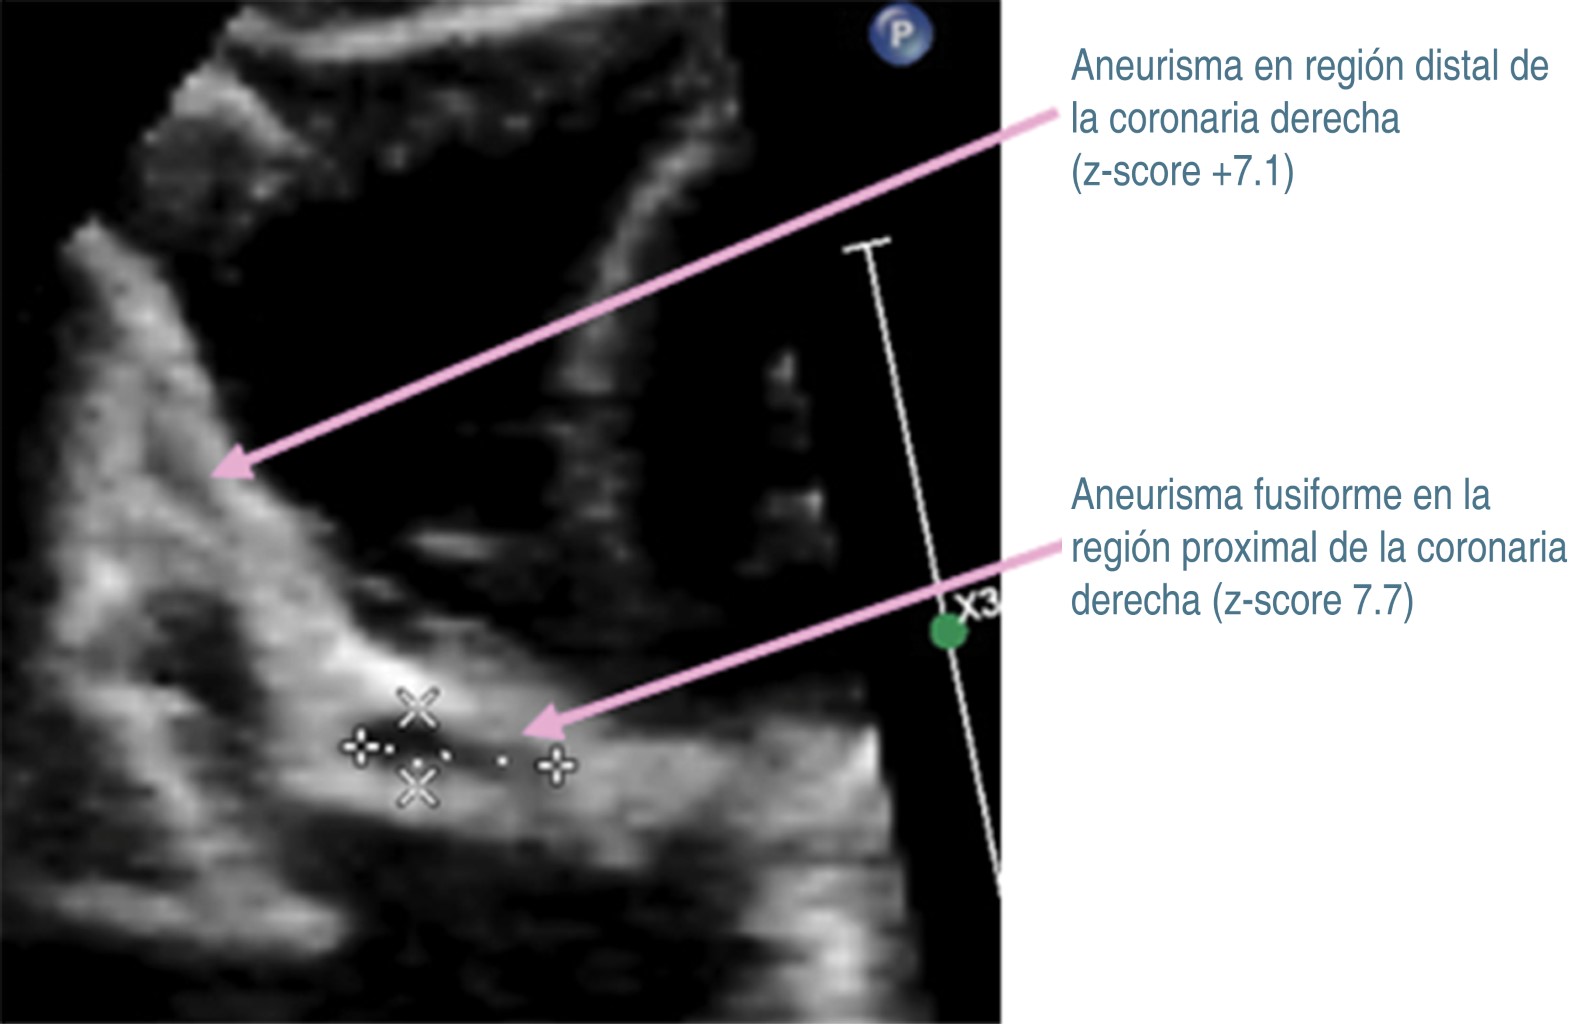

Tras 30 días del padecimiento y por la persistencia de la fiebre, se decide traslado a nuestro hospital. A su ingreso se corrobora fiebre, se ausculta soplo cardiaco holosistólico en mesocardio grado II/VI y soplo sistólico regurgitante en foco tricuspídeo grado II/VI, pero sin repercusión hemodinámica. Se decide continuar con antibióticos, iniciando protocolo de estudio de fiebre de origen a determinar. En nuevos exámenes de laboratorio (Tabla 1, columna B), se determina leucocitosis, neutrofilia, trombocitosis e hipoalbuminemia. Radiografía de tórax, ultrasonido abdominal y tomografía computarizada de cráneo fueron normales. En electrocardiograma se observó crecimiento de cavidades izquierdas, sospechando endocarditis, por lo que se realiza ecocardiograma transtorácico (ECT), con los siguientes hallazgos: persistencia de conducto arterioso; en arteria coronaria izquierda (Figura 1) se observa aneurisma sacular que mide 4.6 mm de ancho y 5.2 mm de longitud (z-score +9.2), así como imagen sugestiva de trombo en su interior. En coronaria derecha (Figura 2), origen: 4.2 mm (z-score +8.6), se observan dos aneurismas fusiformes en la porción proximal, uno mide 9.9 × 53.9 mm (z-score + 7.7), y otro más en la porción distal que mide 7.6 × 3.2 mm (z-score +7.1). Además, se detectó derrame pericárdico laminar y función sistólica ventricular conservada.

Figura 2